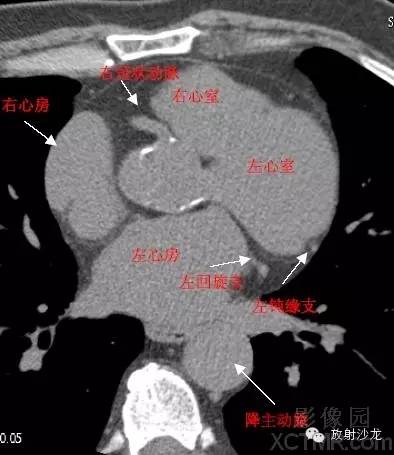

心脏冠状动脉CT解剖中文详细标注

LA -Left Atrium左心房

RA -Right Atrium右心房

LV -Left Ventricle左心室

RV -Right Ventricle右心室

D. Aorta-Descending Aorta降主动脉

LCX -Left Circumflex Artery左回旋支

LMB -Left Obtuse Marginal Branch 左边缘支(钝缘支)

GCV–Great Cardiac Vein心大静脉